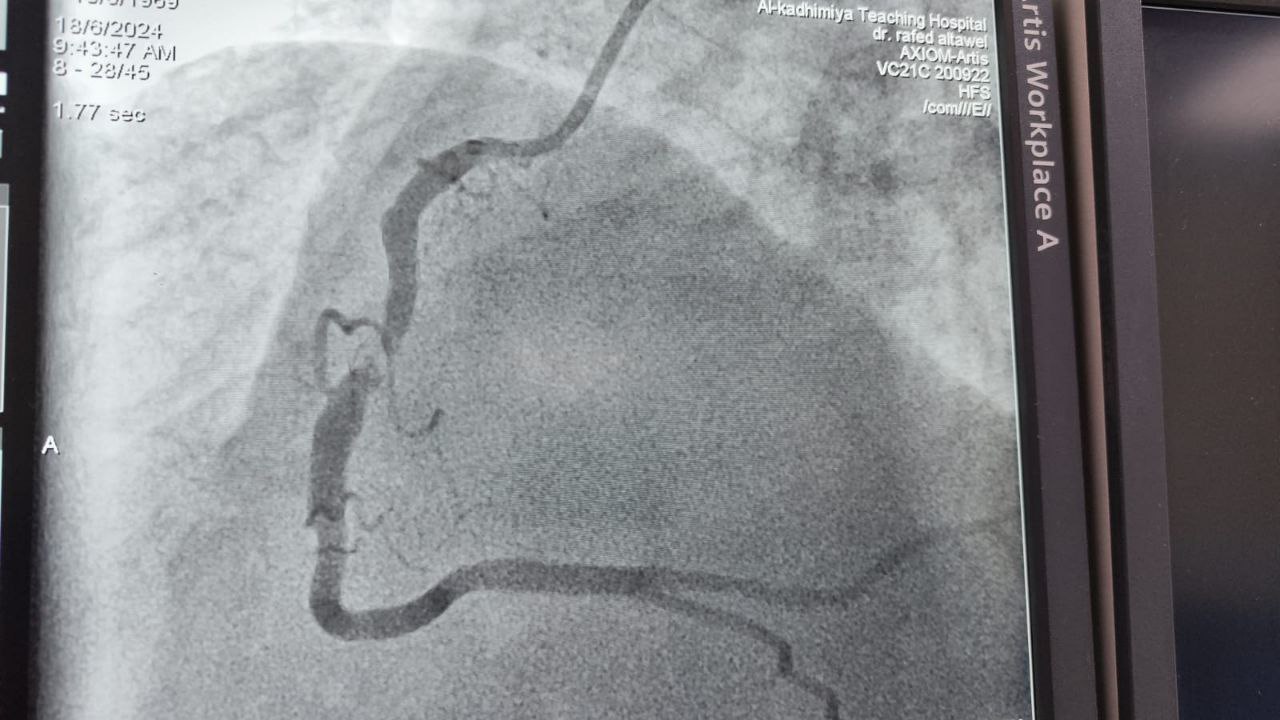

Assistant Professor Dr. Rafid Basheer Al-Tawil, a faculty member in the Department of Internal Medicine at Al-Nahrain College of Medicine, provided a catheterization medical service on the second day of Eid al-Adha at the Catheterization Unit of Al-Imamain Al-Kadhimain Medical City Hospital. The patient, a fifty-year-old Egyptian national, was suffering from a myocardial infarction. A drug-eluting stent was successfully placed in the right coronary artery. After the catheterization procedure, the patient was discharged in good health, praise be to God.